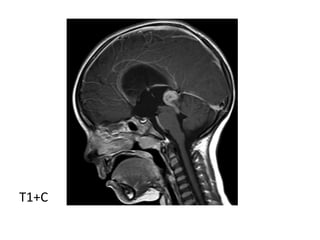

b) MRI

-T1 : isointense or slightly hyperintense to adjacent

brain

-T2 : isointense or slightly hyperintense to adjacent

brain, may have areas of cyst formation, central

calcification appears low signal (engulfed pineal

gland)

-T1+C : vivid and homogeneous

T1

T1+C